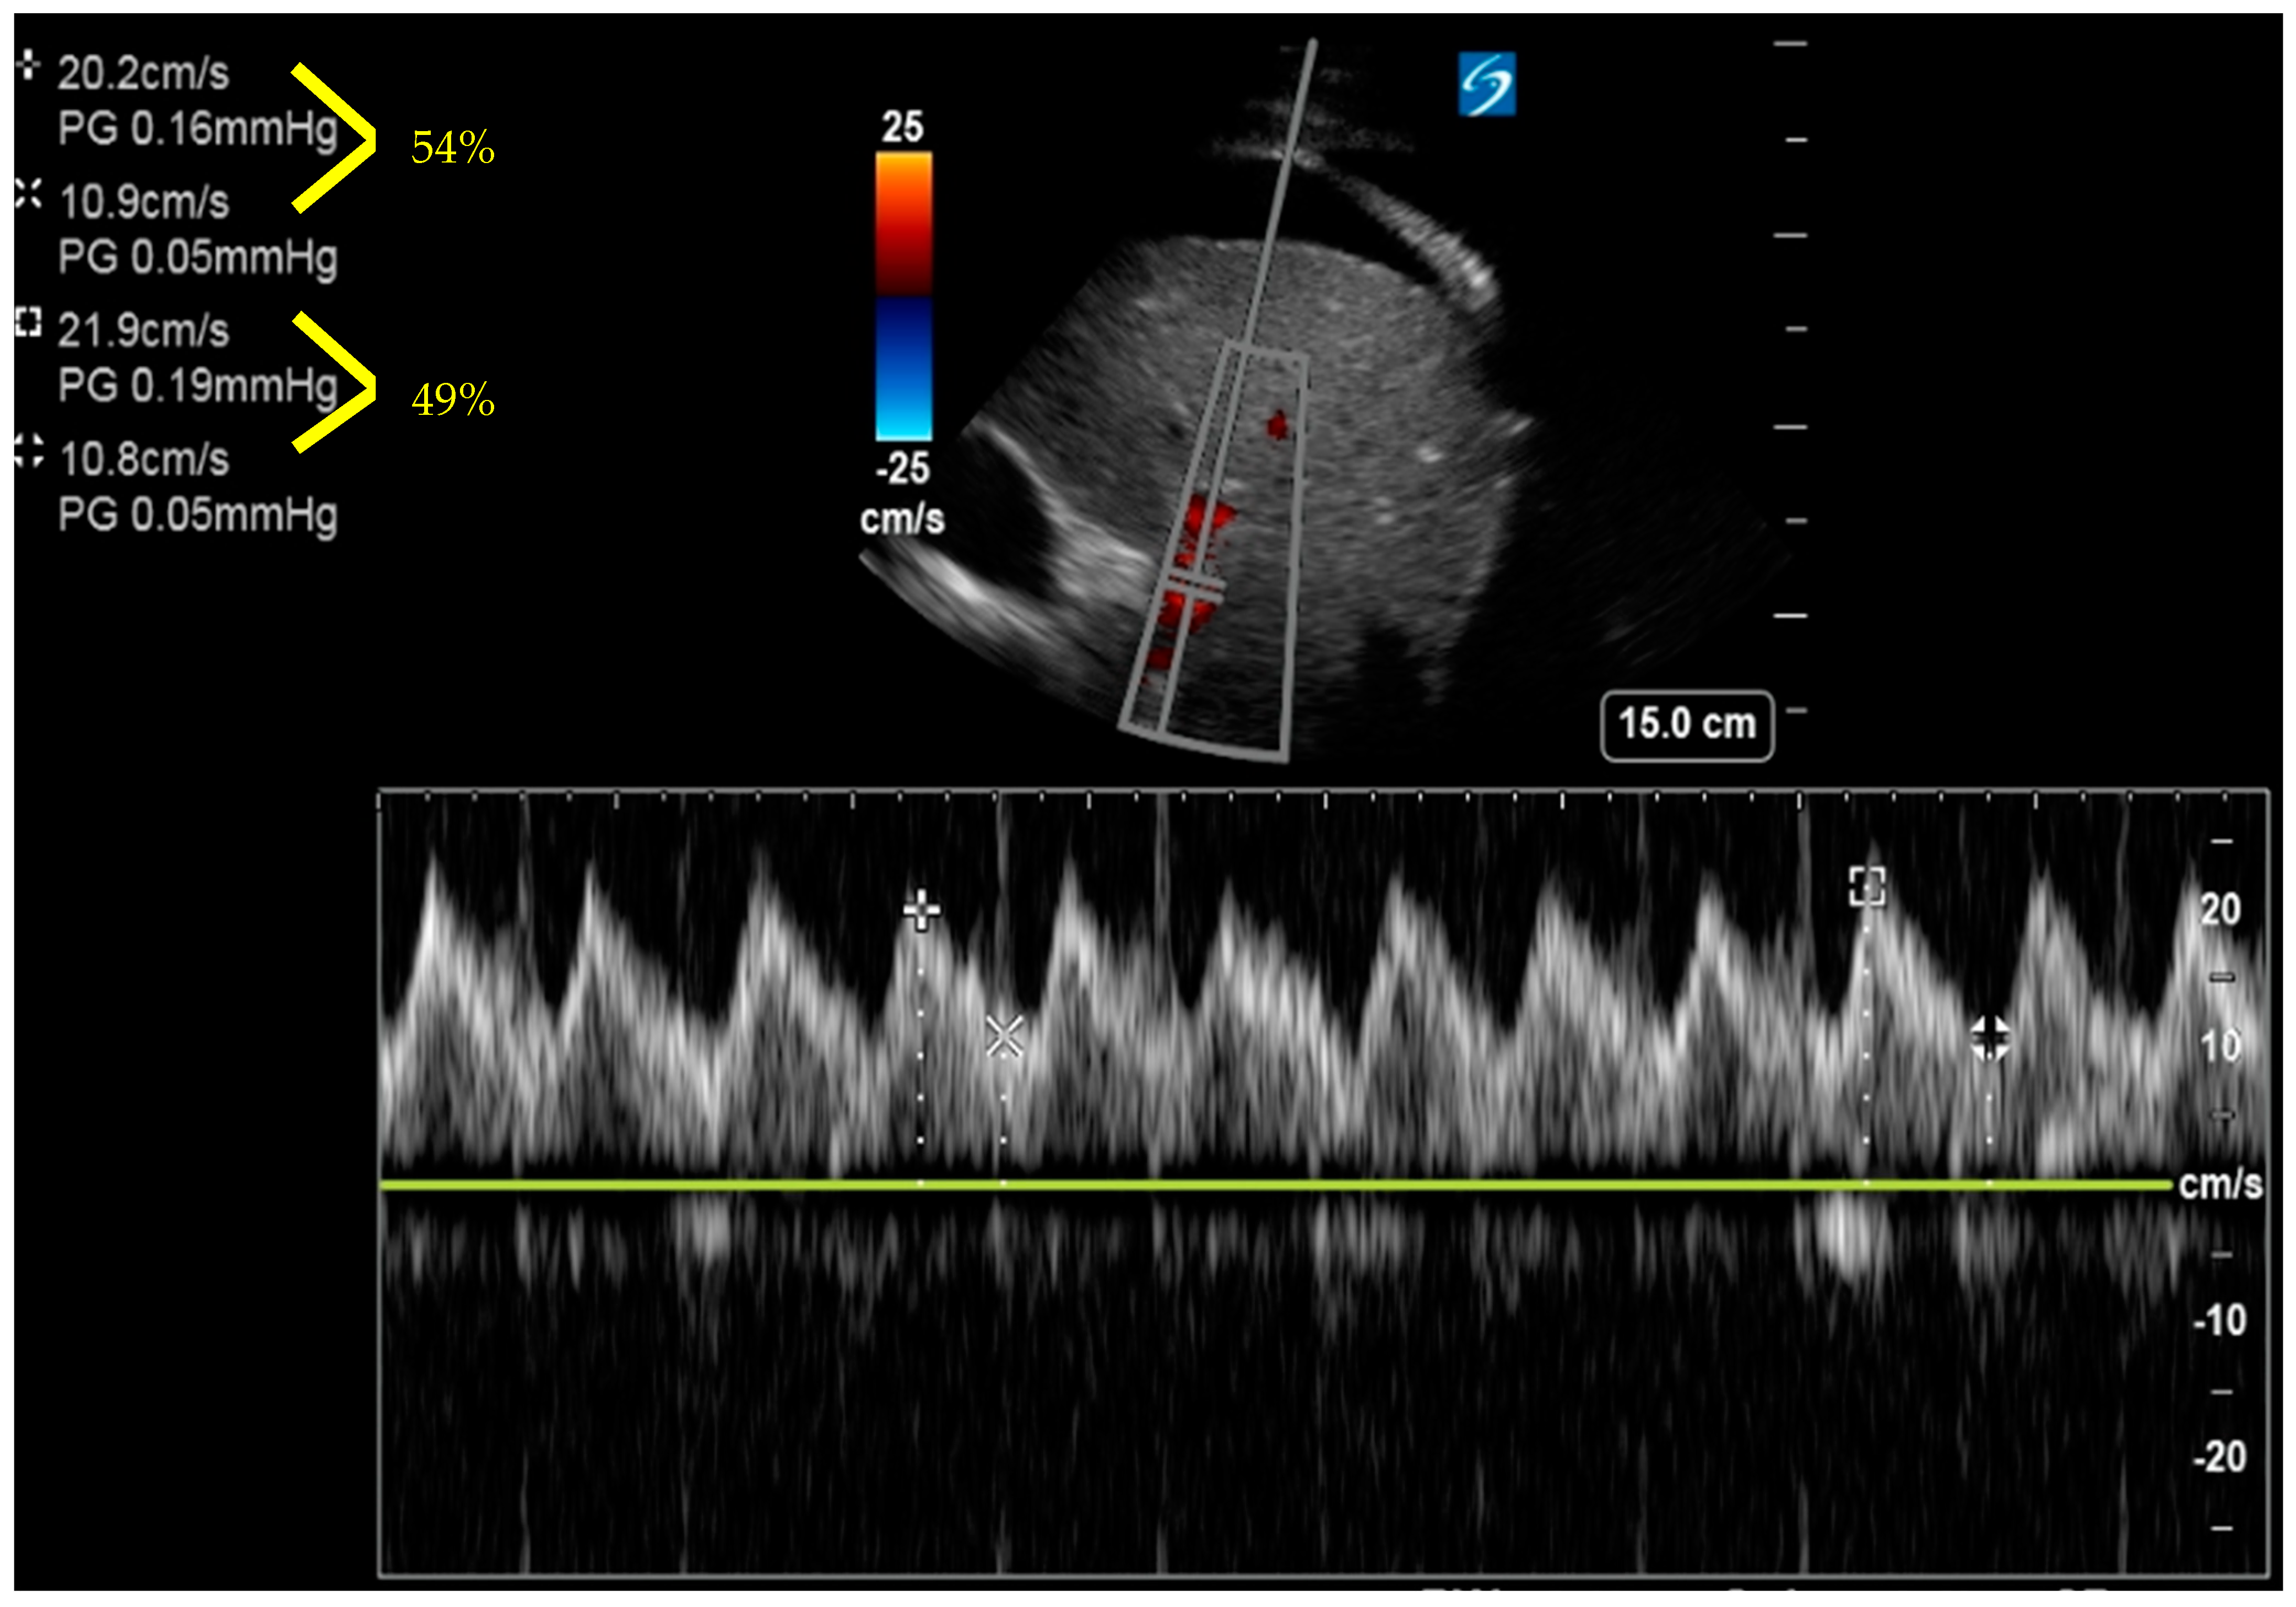

6. Venous Excess Ultrasound Score

- Beaubien-Souligny, W.; Rola, P.; Haycock, K.; Bouchard, J.; Lamarche, Y.; Spiegel, R.; Denault, A.Y. Quantifying systemic congestion with Point-Of-Care ultrasound: Development of the venous excess ultrasound grading system. Ultrasound J. 2020, 12, 16. [Google Scholar] [CrossRef]

- Longino, A.; Martin, K.; Leyba, K.; Siegel, G.; Gill, E.; Douglas, I.S.; Burke, J. Correlation between the VExUS score and right atrial pressure: A pilot prospective observational study. Crit. Care 2023, 27, 205. [Google Scholar] [CrossRef]

- Spiegel, R.; Teeter, W.; Sullivan, S.; Tupchong, K.; Mohammed, N.; Sutherland, M.; Leibner, E.; Rola, P.; Galvagno, S.M.; Jr Murthi, S.B. The use of venous Doppler to predict adverse kidney events in a general ICU cohort. Crit. Care 2020, 24, 615. [Google Scholar] [CrossRef]

- Andrei, S.; Bahr, P.A.; Nguyen, M.; Bouhemad, B.; Guinot, P.G. Prevalence of systemic venous congestion assessed by Venous Excess Ultrasound Grading System (VExUS) and association with acute kidney injury in a general ICU cohort: A prospective multicentric study. Crit. Care 2023, 27, 224. [Google Scholar] [CrossRef]

- Argaiz, E.R.; Rola, P.; Gamba, G. Dynamic Changes in Portal Vein Flow during Decongestion in Patients with Heart Failure and Cardio-Renal Syndrome: A POCUS Case Series. Cardiorenal Med. 2021, 11, 59–66. [Google Scholar] [CrossRef]

- Rola, P.; Miralles-Aguiar, F.; Argaiz, E.; Beaubien-Souligny, W.; Haycock, K.; Karimov, T.; Dinh, V.A.; Spiegel, R. Clinical applications of the venous excess ultrasound (VExUS) score: Conceptual review and case series. Ultrasound J. 2021, 13, 32. [Google Scholar] [CrossRef] [PubMed]